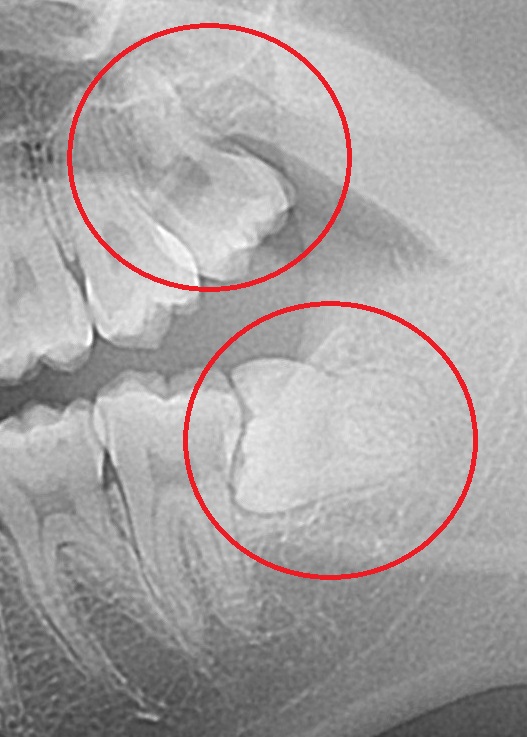

20代女性 親知らずの抜歯希望です。

左側の上下の抜歯です。

下の親知らずは横向きに生えてしまっています。

お口の中の写真はこんな感じ。

赤丸の位置に、少しだけ歯の頭が見えます。